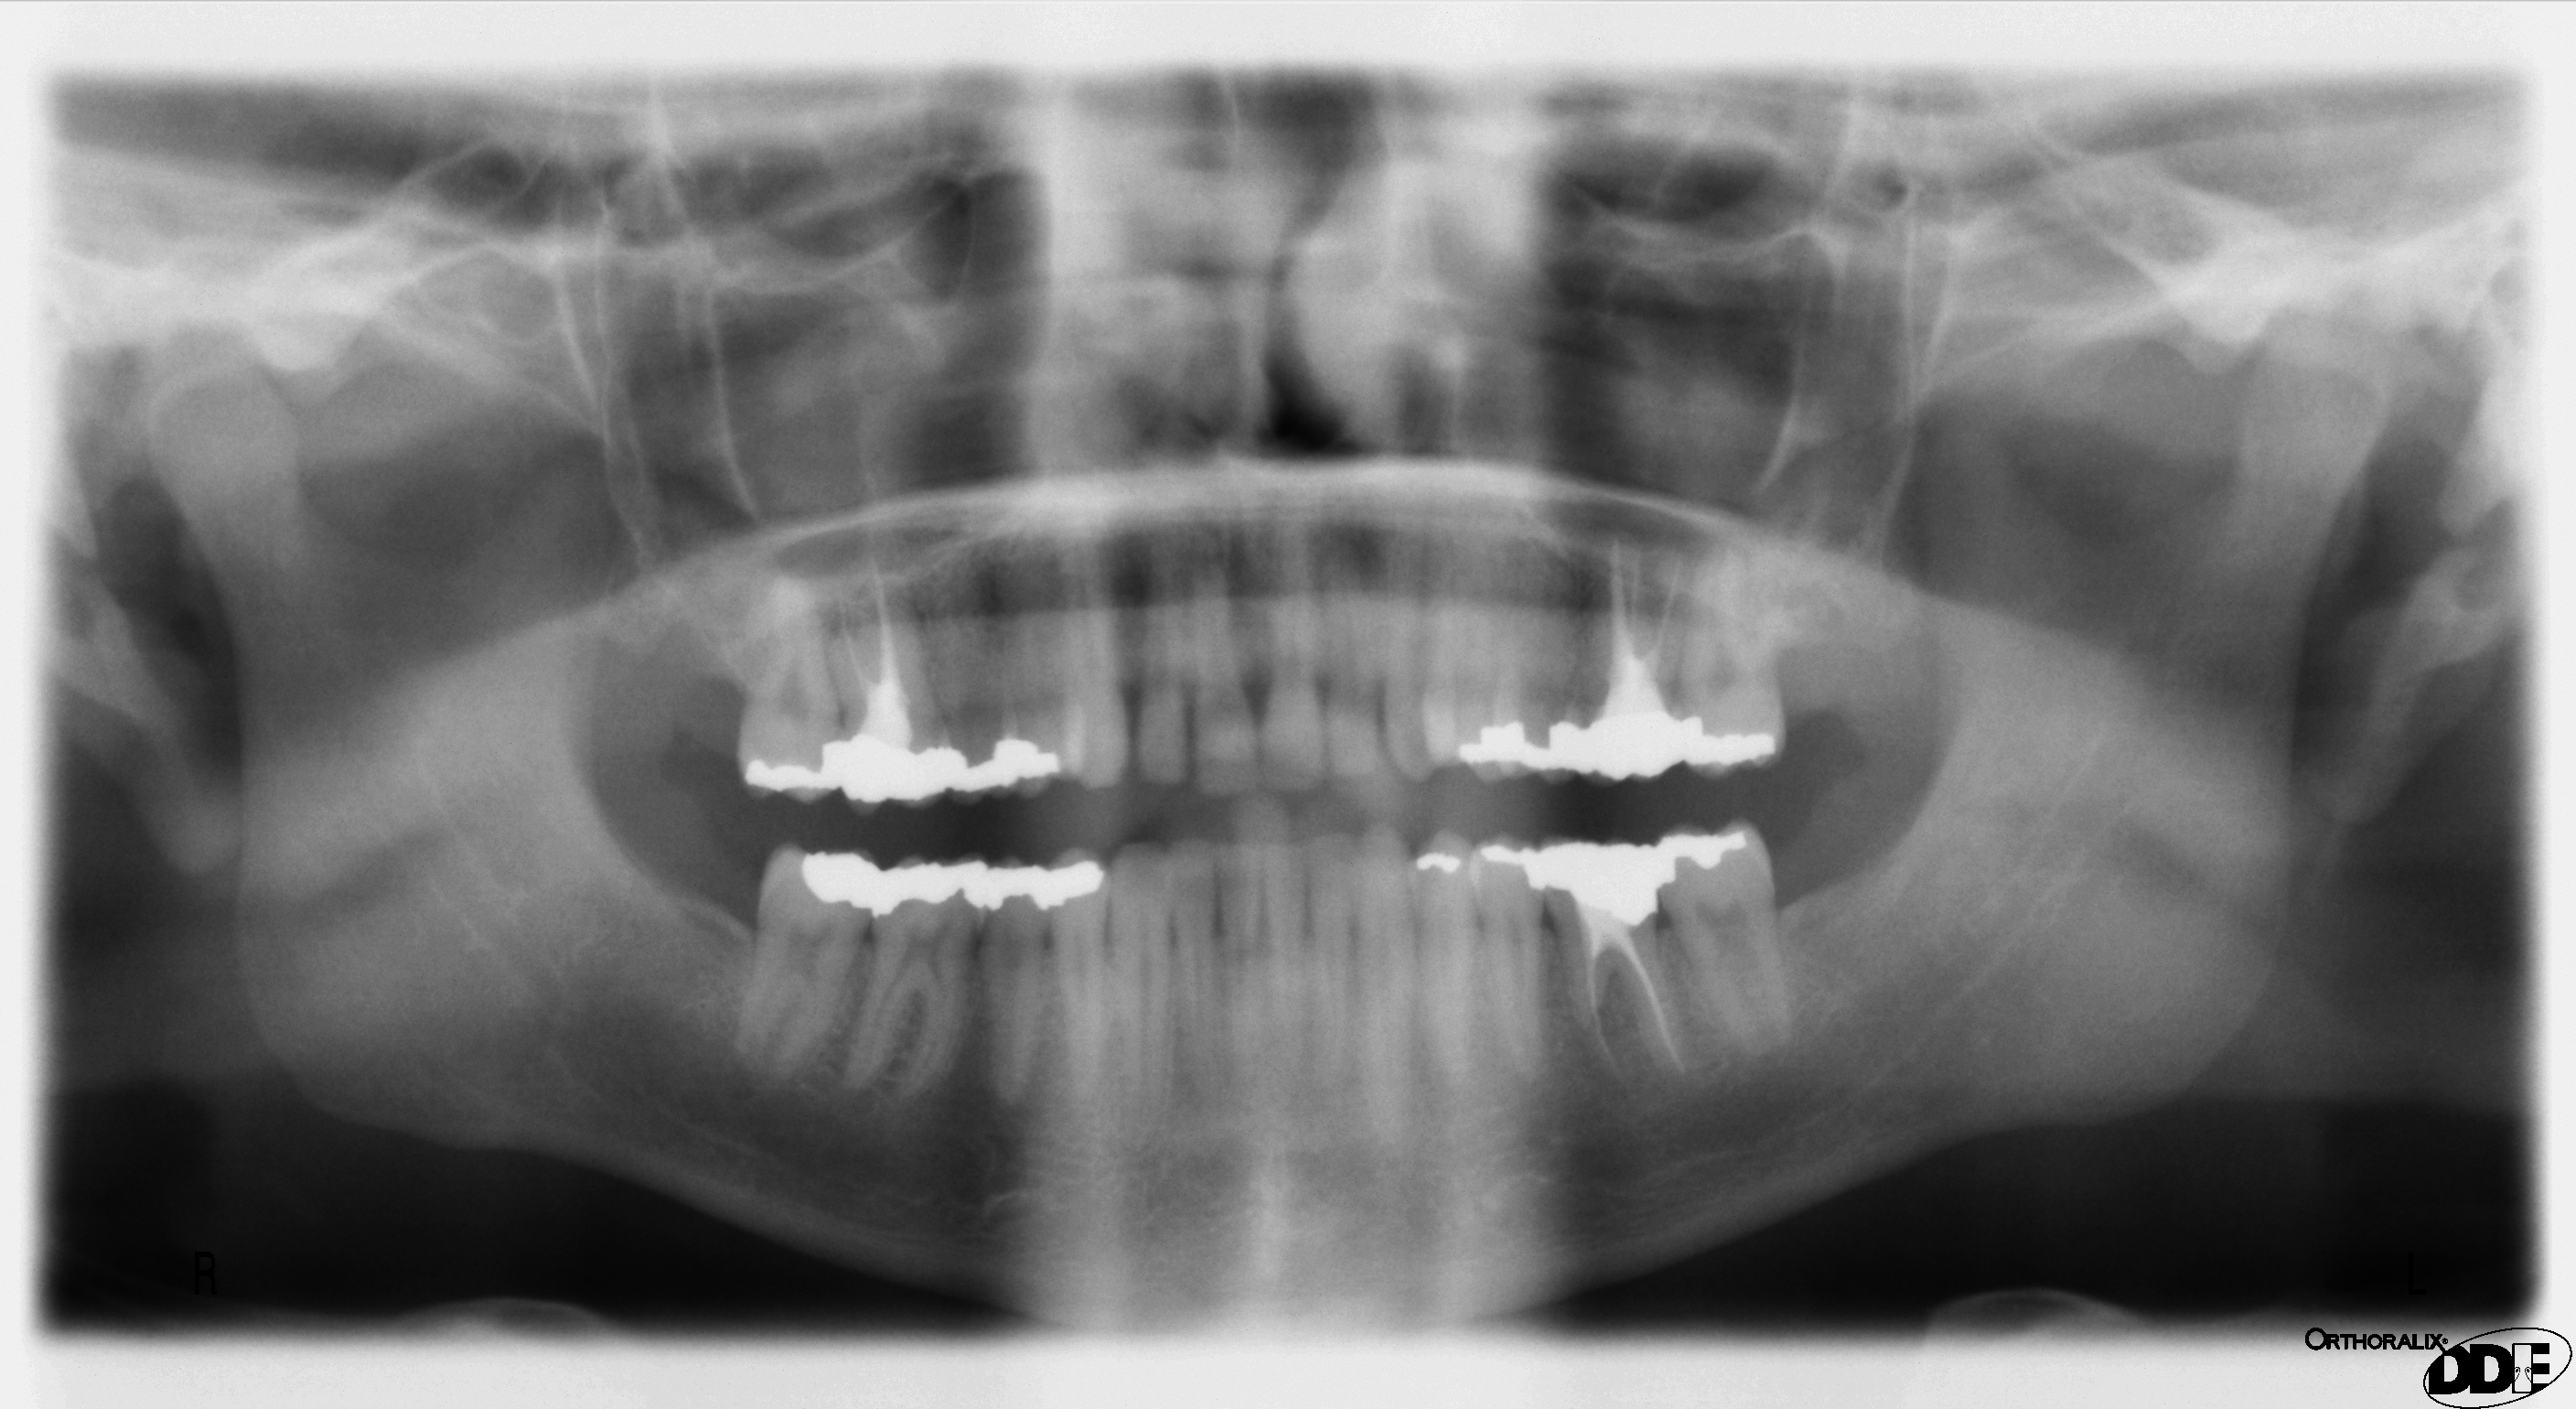

OPG daje przegląd szczęki, żuchwy, zębów i części struktur sąsiednich. Pomaga zaplanować dalsze kroki, ale ma ograniczenia geometrii i ostrości.

Przegląd szczęki i żuchwy: zęby zatrzymane, ósemki, zmiany kostne, stan ogólny uzębienia i planowanie dalszej diagnostyki.

W OPG znaczenie mają linia frankfurcka, pozycja języka, stabilizacja głowy i usunięcie metalu.

Brak kontaktu języka z podniebieniem tworzy ciemny pas powietrza nad korzeniami górnych zębów.

OPG jako mapa szczęki, żuchwy, zębów, zatok i stawów skroniowo-żuchwowych.